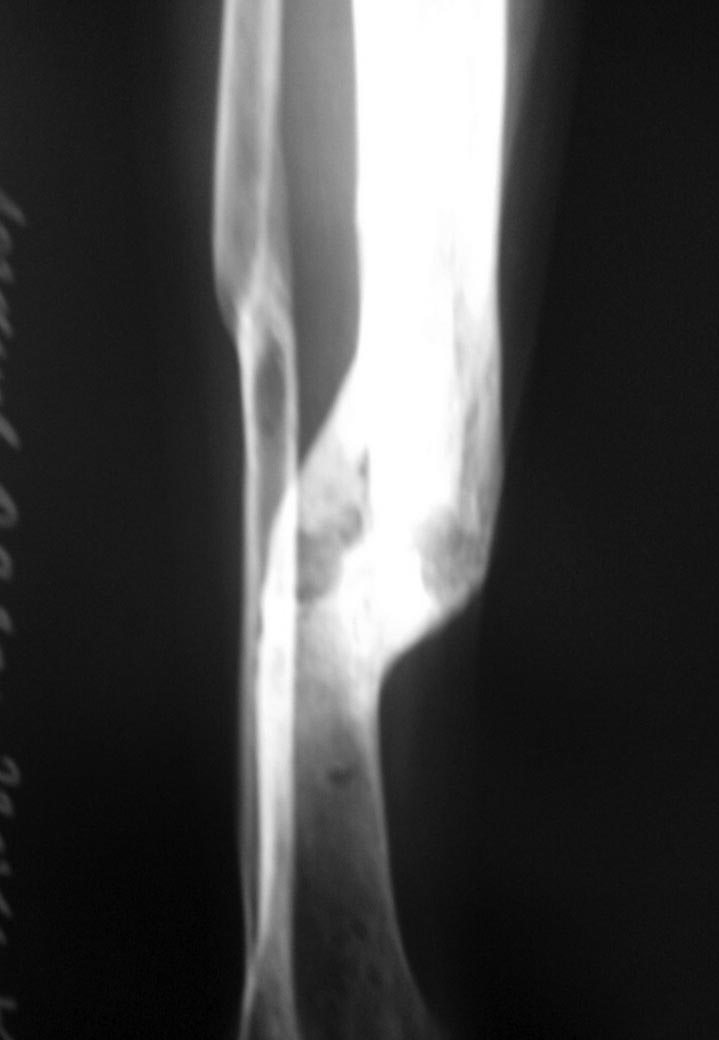

[Ortho] сложный перелом плеча - перелом плеча после неправильно сросшегося перелома

добавлю снимки голени